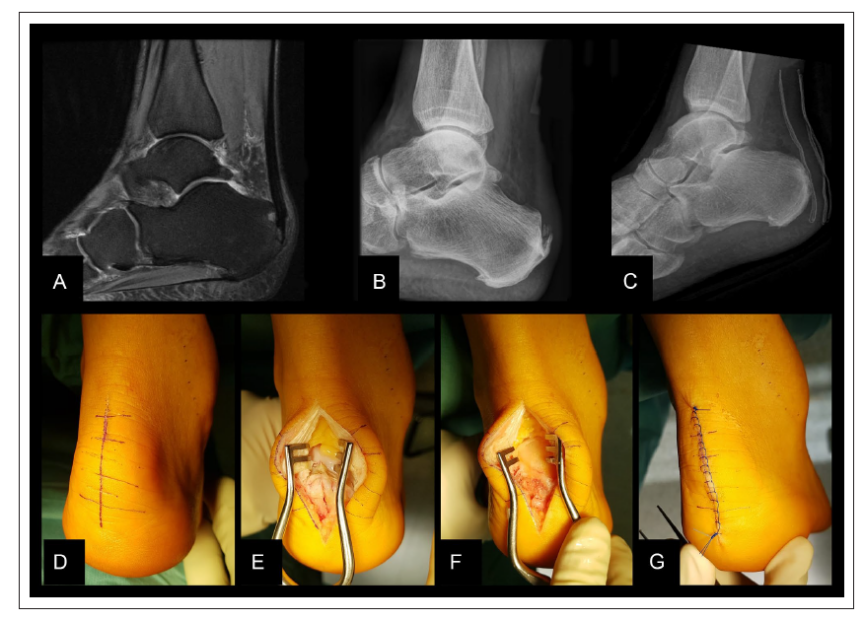

Haglund综合征包括Haglund畸形、跟骨后滑囊炎、跟腱皮下滑囊炎、止点性跟腱炎。诊断依赖于临床表现和影像学检查。手术治疗方法包括跟骨后结节切除、跟腱止点重建和跟骨背侧闭合楔形截骨。根据患者具体情况不同,选择合适的手术方法。

Haglund综合征的诊断

X:Fowler and Philips angle,44°-69°

CLA角:Chauveaux-Liet  Angle,CLA=α-β,>12°怀疑,X/Y值:<2.5高度怀疑

FPA和PPL不可靠,Haglund综合征与跟腱钙化和跟骨后方骨刺关系密切。

开放外侧手术入路

关节镜入路

后正中入路

外侧入路切除跟骨内侧骨膜比较困难,采用正中劈开跟腱入路行 Haglund 畸形切除术联合跟腱止点重建术,取得了良好疗效

止点变性和钙化严重导致彻底清理后跟腱止点缺损超过50%时需要行跟腱止点重建。

50%-70%的跟腱止点切断,一枚锚钉固定:

跟腱完全从止点切开,用两枚单排锚钉固定: